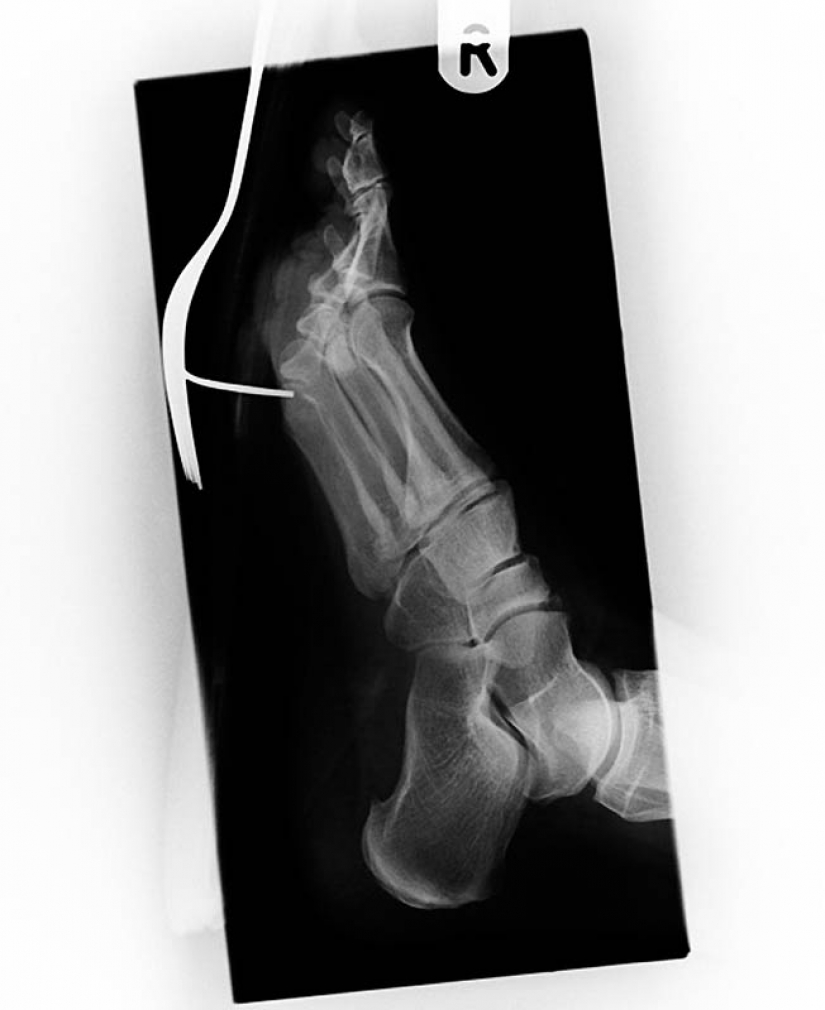

3. Vintage x-ray de el soldado de la guerra Anglo-Boer (1899-1902) con una herida de bala. La bala alojada en el metatarso entre el pulgar y el segundo dedo.